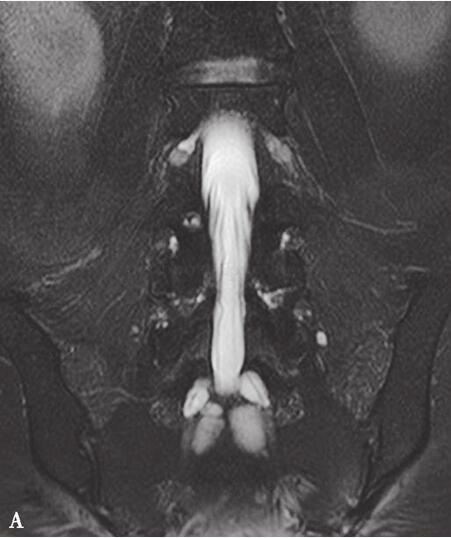

北京医院腰椎MRI:腰椎生理曲度存在,各椎间隙无变窄,各椎间盘未见向后突出,椎间孔无变窄。脊髓圆锥形态、信号未见明显异常。椎管无明显狭窄。骶管内可见多发椭圆形液体信号,边界清楚,T1加权像呈低信号,T2加权像呈高信号。T2加权像显示神经根周围液体较多(图31-1)。臀部肌肉萎缩,有脂肪变性。

图31-1 腰椎MRI平扫:(A)冠状位T2WI压脂像显示神经根周围液体较多;(B)矢状位T2WI压脂像显示椎管内可见多发椭圆形水样信号影,边界清楚